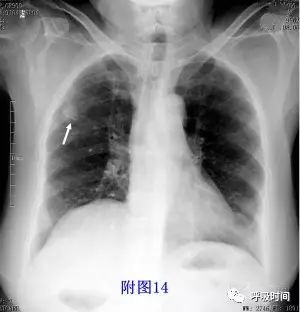

图片

图 14 病灶直径<30 mm,结节影——手术病理:结核球